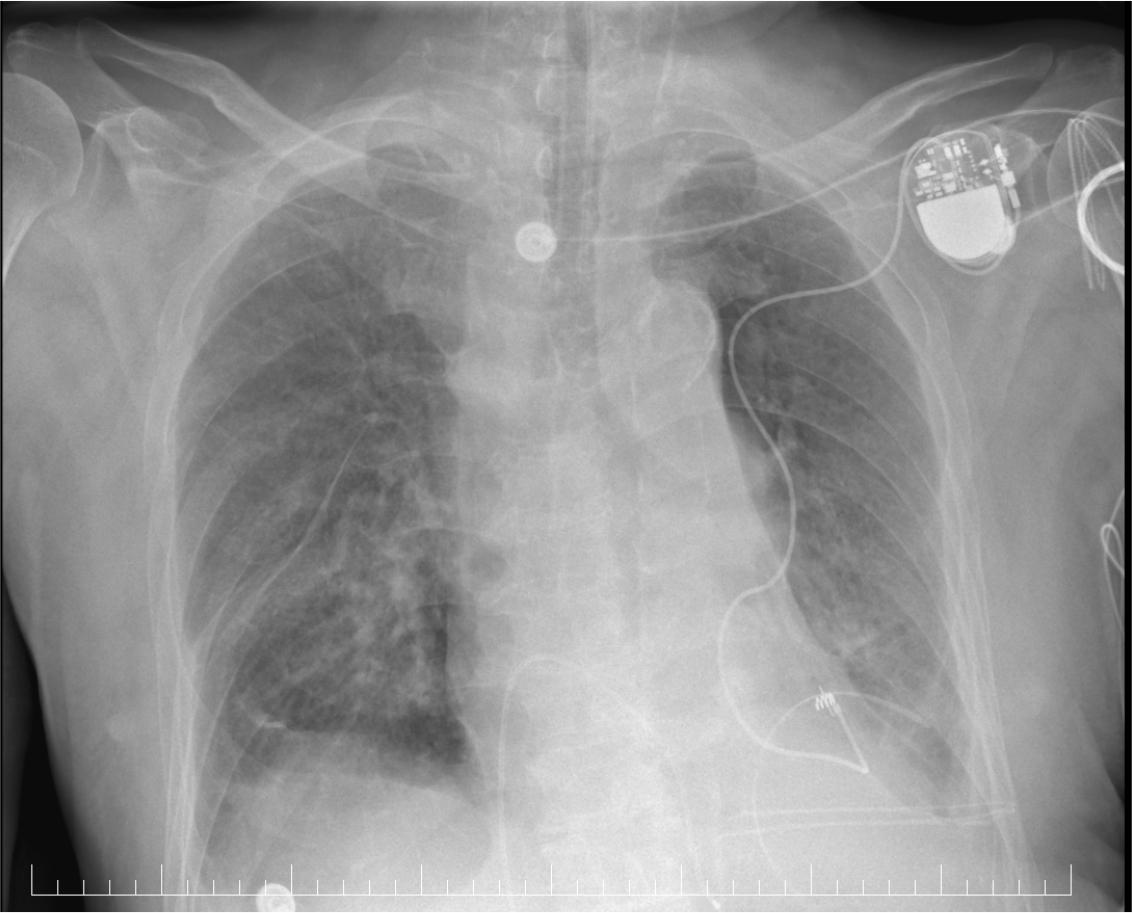

X ray-pacemaker and epicardial lead placement.

Postoperative chest X-ray confirmed correct epicardial lead placement with no pneumothorax or complications (Summary Figure 5). The patient remained hemodynamically stable, was extubated within 24 hours, and the ECG showed atrial fibrillation with left bundle branch block. (Summary Figure 1). Hemodialysis sessions were performed as scheduled. Laboratory tests showed stable grade II anemia, persistent azotemia, and elevated CRP, with no clinical or paraclinical signs of infection. Serial chest radiographs confirmed pulmonary status and lead placement.